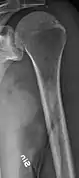

Multiple myeloma in the upper arm

Humerus with multiple myeloma lesions

Same humerus before, with just subtle lesions

The diagnostic examination of a person with suspected multiple myeloma typically includes a skeletal survey. This is a series of X-rays of the skull, axial skeleton, and proximal long bones. Myeloma activity sometimes appears as "lytic lesions" (with local disappearance of normal bone due to resorption). And on the skull X-ray as "punched-out lesions" (pepper-pot skull). Lesions may also be sclerotic, which is seen as radiodense.[47] Overall, the radiodensity of myeloma is between −30 and 120 Hounsfield units (HU).[48] Magnetic resonance imaging is more sensitive than simple X-rays in the detection of lytic lesions, and may supersede a skeletal survey, especially when vertebral disease is suspected. Occasionally, a CT scan is performed to measure the size of soft-tissue plasmacytomas. Bone scans are typically not of any additional value in the workup of people with myeloma (no new bone formation; lytic lesions not well visualized on bone scan).